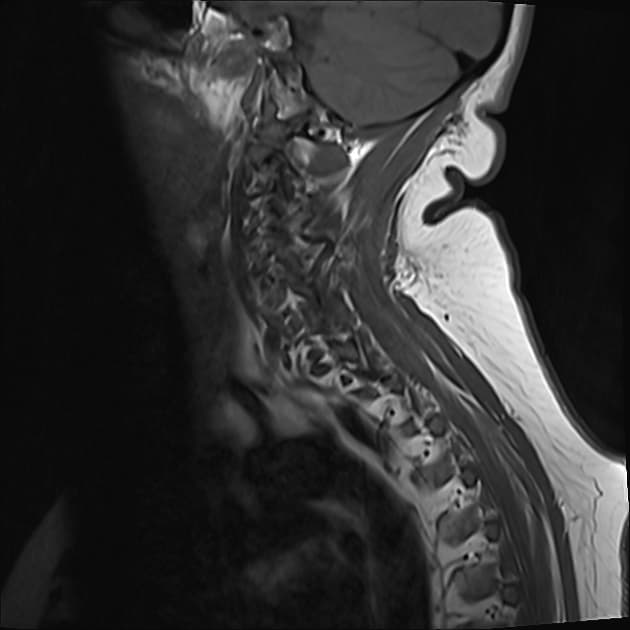

Xơ cứng rải rác dạng u

Mất thị lực mắt phải từng bước, liệt nhẹ cả hai chi dưới, và mất kiểm soát tiểu tiện, đại tiện trong 2 năm qua.

- Ghi nhận nhiều ổ tổn thương bất thường về tín hiệu nội nhu mô (ít nhất 5 ổ) tại vùng ranh giới chất xám-chất trắng ở cả hai bán cầu đại não, trong đó có hai ổ bên phải và ba ổ bên trái.

- Các tổn thương này cho tín hiệu tăng trên hình ảnh trọng T2 và tín hiệu giảm trên hình ảnh trọng T1, có phù nhẹ vùng xung quanh.

- Không thấy hạn chế khuếch tán (restricted diffusion).

- Không thấy hiện tượng nở bóng trên T2* GRE (T2* GRE blooming artifact).

- Trên hình ảnh sau tiêm thuốc cản quang, các tổn thương cho thấy bắt thuốc dạng viền không hoàn chỉnh (incomplete ring enhancement).

- Tổn thương ở thùy trán trái lan sang phía bên trái của gối thể chai (genu of the corpus callosum).

Xét theo lâm sàng và đặc điểm hình ảnh, chẩn đoán khả dĩ nhất là một rối loạn mất bao myelin (demyelinating disorder), cụ thể là xơ cứng rải rác dạng u (tumefactive multiple sclerosis).

- "Xơ cứng rải rác dạng u có thể bắt chước u não về mặt lâm sàng và hình ảnh học."

- "Hiện tượng bắt thuốc dạng viền không hoàn chỉnh, không hạn chế khuếch tán và không có hiện tượng nở bóng trên T2* giúp phân biệt với áp xe hoặc u."

- "Các tổn thương ở vùng ranh giới chất xám-chất trắng kèm tổn thương thể chai là đặc trưng của bệnh mất myelin."